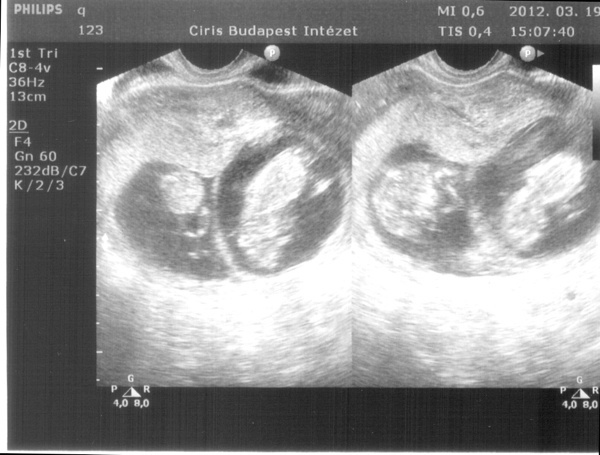

Ja Suti vicces, mert az en ferjem akarja az ikreket nagyon, es egy honapja mondom neki, hogy nem lesznek ikrek ,mert csak egy petesejt erik spontan ciklusban, erre kijovok es mondom neki, hogy kepzeld ketto is erik. O meg: na ugye hogy megmondtam, hogy ikreim lesznek. Bolond ember na